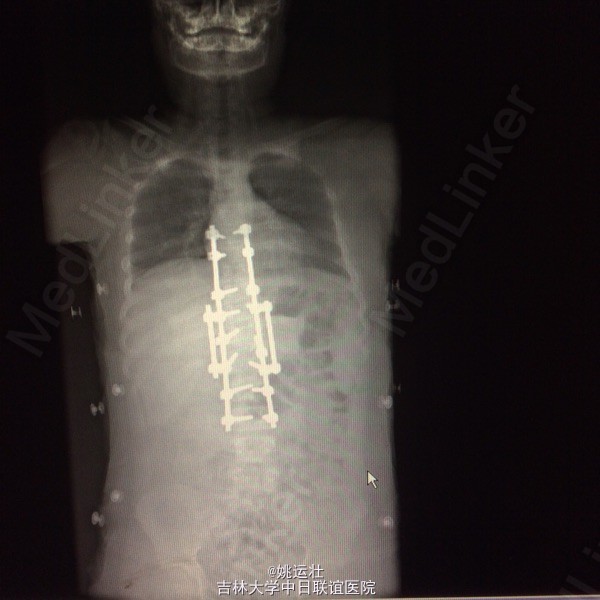

站立位腰背部疼痛5个月 五月前检查发现腰背部畸形伴疼痛,未行特殊治疗。

患者呈向心性肥胖,眼角略上斜,下颌小,上下牙间距大,闭齿音发音不清,性早熟,外阴幼稚,大小阴唇发育不良,手脚小胖,指端纤细,余查体无明显异常。 辅助检查:胸9-10胸12-腰1椎体融合、胸11呈半椎体,椎管内脊髓未见明显信号异常.

胸椎半椎体畸形 左侧第10肋骨缺如 隐形骶椎裂 双下肢膝外翻 双下肢肌挛缩症 脊柱畸形术,胸5、6、8、9腰1-2-3双侧椎弓根螺钉,去除胸11-12后方椎板,胸12半椎体及上下间隙间盘去除,椎间隙植骨。